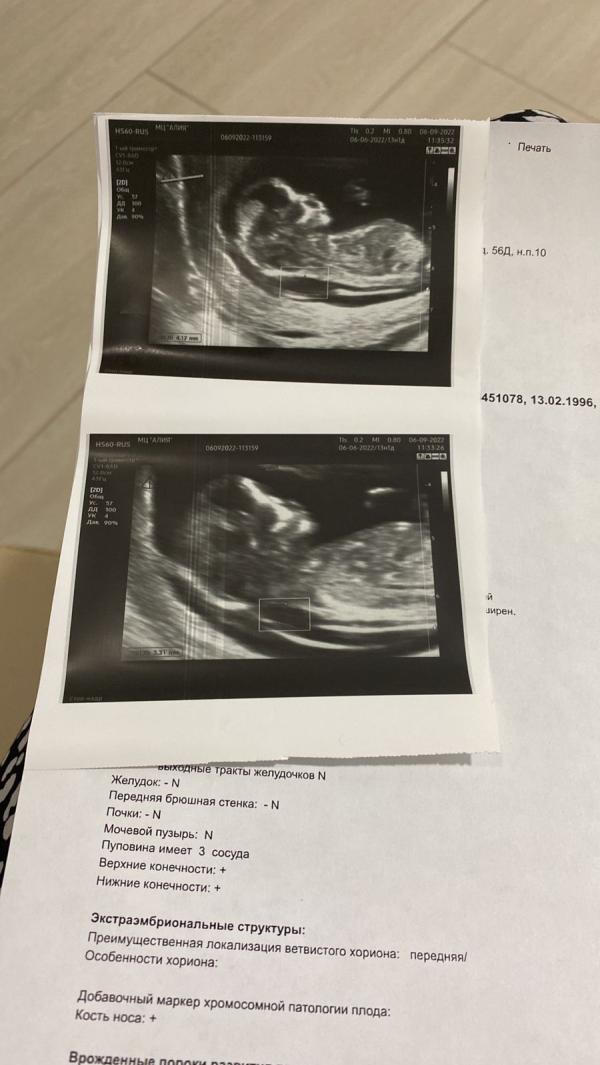

Утолщение твп это маркер синдрома Дауна.

Это утолщение твп. Мне поставили то же самоё на первом скринингее. Отправили к генетику. Генетик в свою очередь предложил даже настоял на проколе. Но я пока не согласилась на это.

@mika_erlan у меня 3,3 был на первом скрининге в 12 недель.